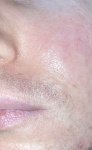

1 пик 2 года назад, второй соответственно сейчас

Более четкий второй пик*

Начали на лице, спине и груди. После 19 на спине они постепенно пропали, сейчас их очень редко там увидишь. На груди есть до сих пор, и на ней прыщи очень маленькие, где-то 0.5-1.5мм и пару больших (примерно как на пике). На лице появляются обыкновенные угри, иногда и белые с гнойниками которые побаливают.